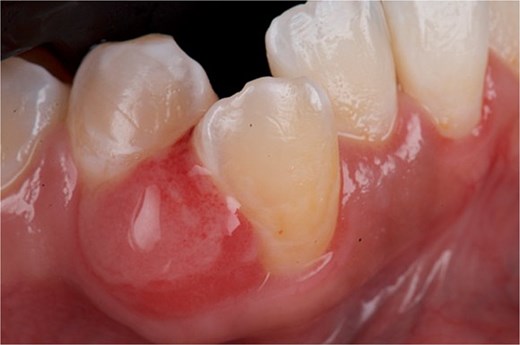

A 29-year-old female patient with no pathological history and healthy periodontium visited the dental clinic with the following complaint: ‘When I was pregnant, a small lump appeared on my gum that bled and would not go away.’ Intraoral examination revealed a mucogingival tissue growth on the attached gum, which was firm, oval, fibrous, smooth, and without signs of active ulceration, measuring ~ 1 × 0.5 cm. The lesion originated at the base of the papilla and part of the adjacent masticatory mucosa, presenting a pedunculated base that extended to the interproximal region of teeth 43 and 44, with erythematous coloration and whitish areas (Fig. 5). The patient reported pain on palpation, with no history of trauma or surgery in the area. A digital periapical radiograph was taken to rule out periodontal or infectious pathology at the bone level.

Front view of the clinical image of the intraoral lesion: Growth of mucogingival tissue in the attached gingiva, with a firm, oval, fibrous, smooth appearance and without signs of active ulceration.